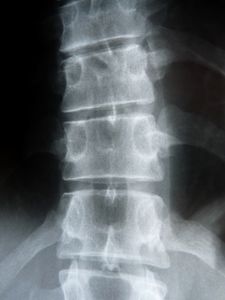

Röntgenbild der Wirbelsäule: Graphen hilft (Foto: pixelio.de/Dieter Schütz) |

Rom (pte016/21.02.2018/10:30) Mithilfe nanotechnisch hergestellter Plättchen aus dem Kohlenstoffmaterial Graphen kann geschädigtes Knochengewebe repariert und in seine ursprüngliche Form gebracht werden. Das haben Forscher der Facoltà di Medicina e Chirurgia an der Università Cattolica del Sacro Cuore http://unicatt.it und des Istituto dei Sistemi Complessi http://www.isc.cnr.it herausgefunden.